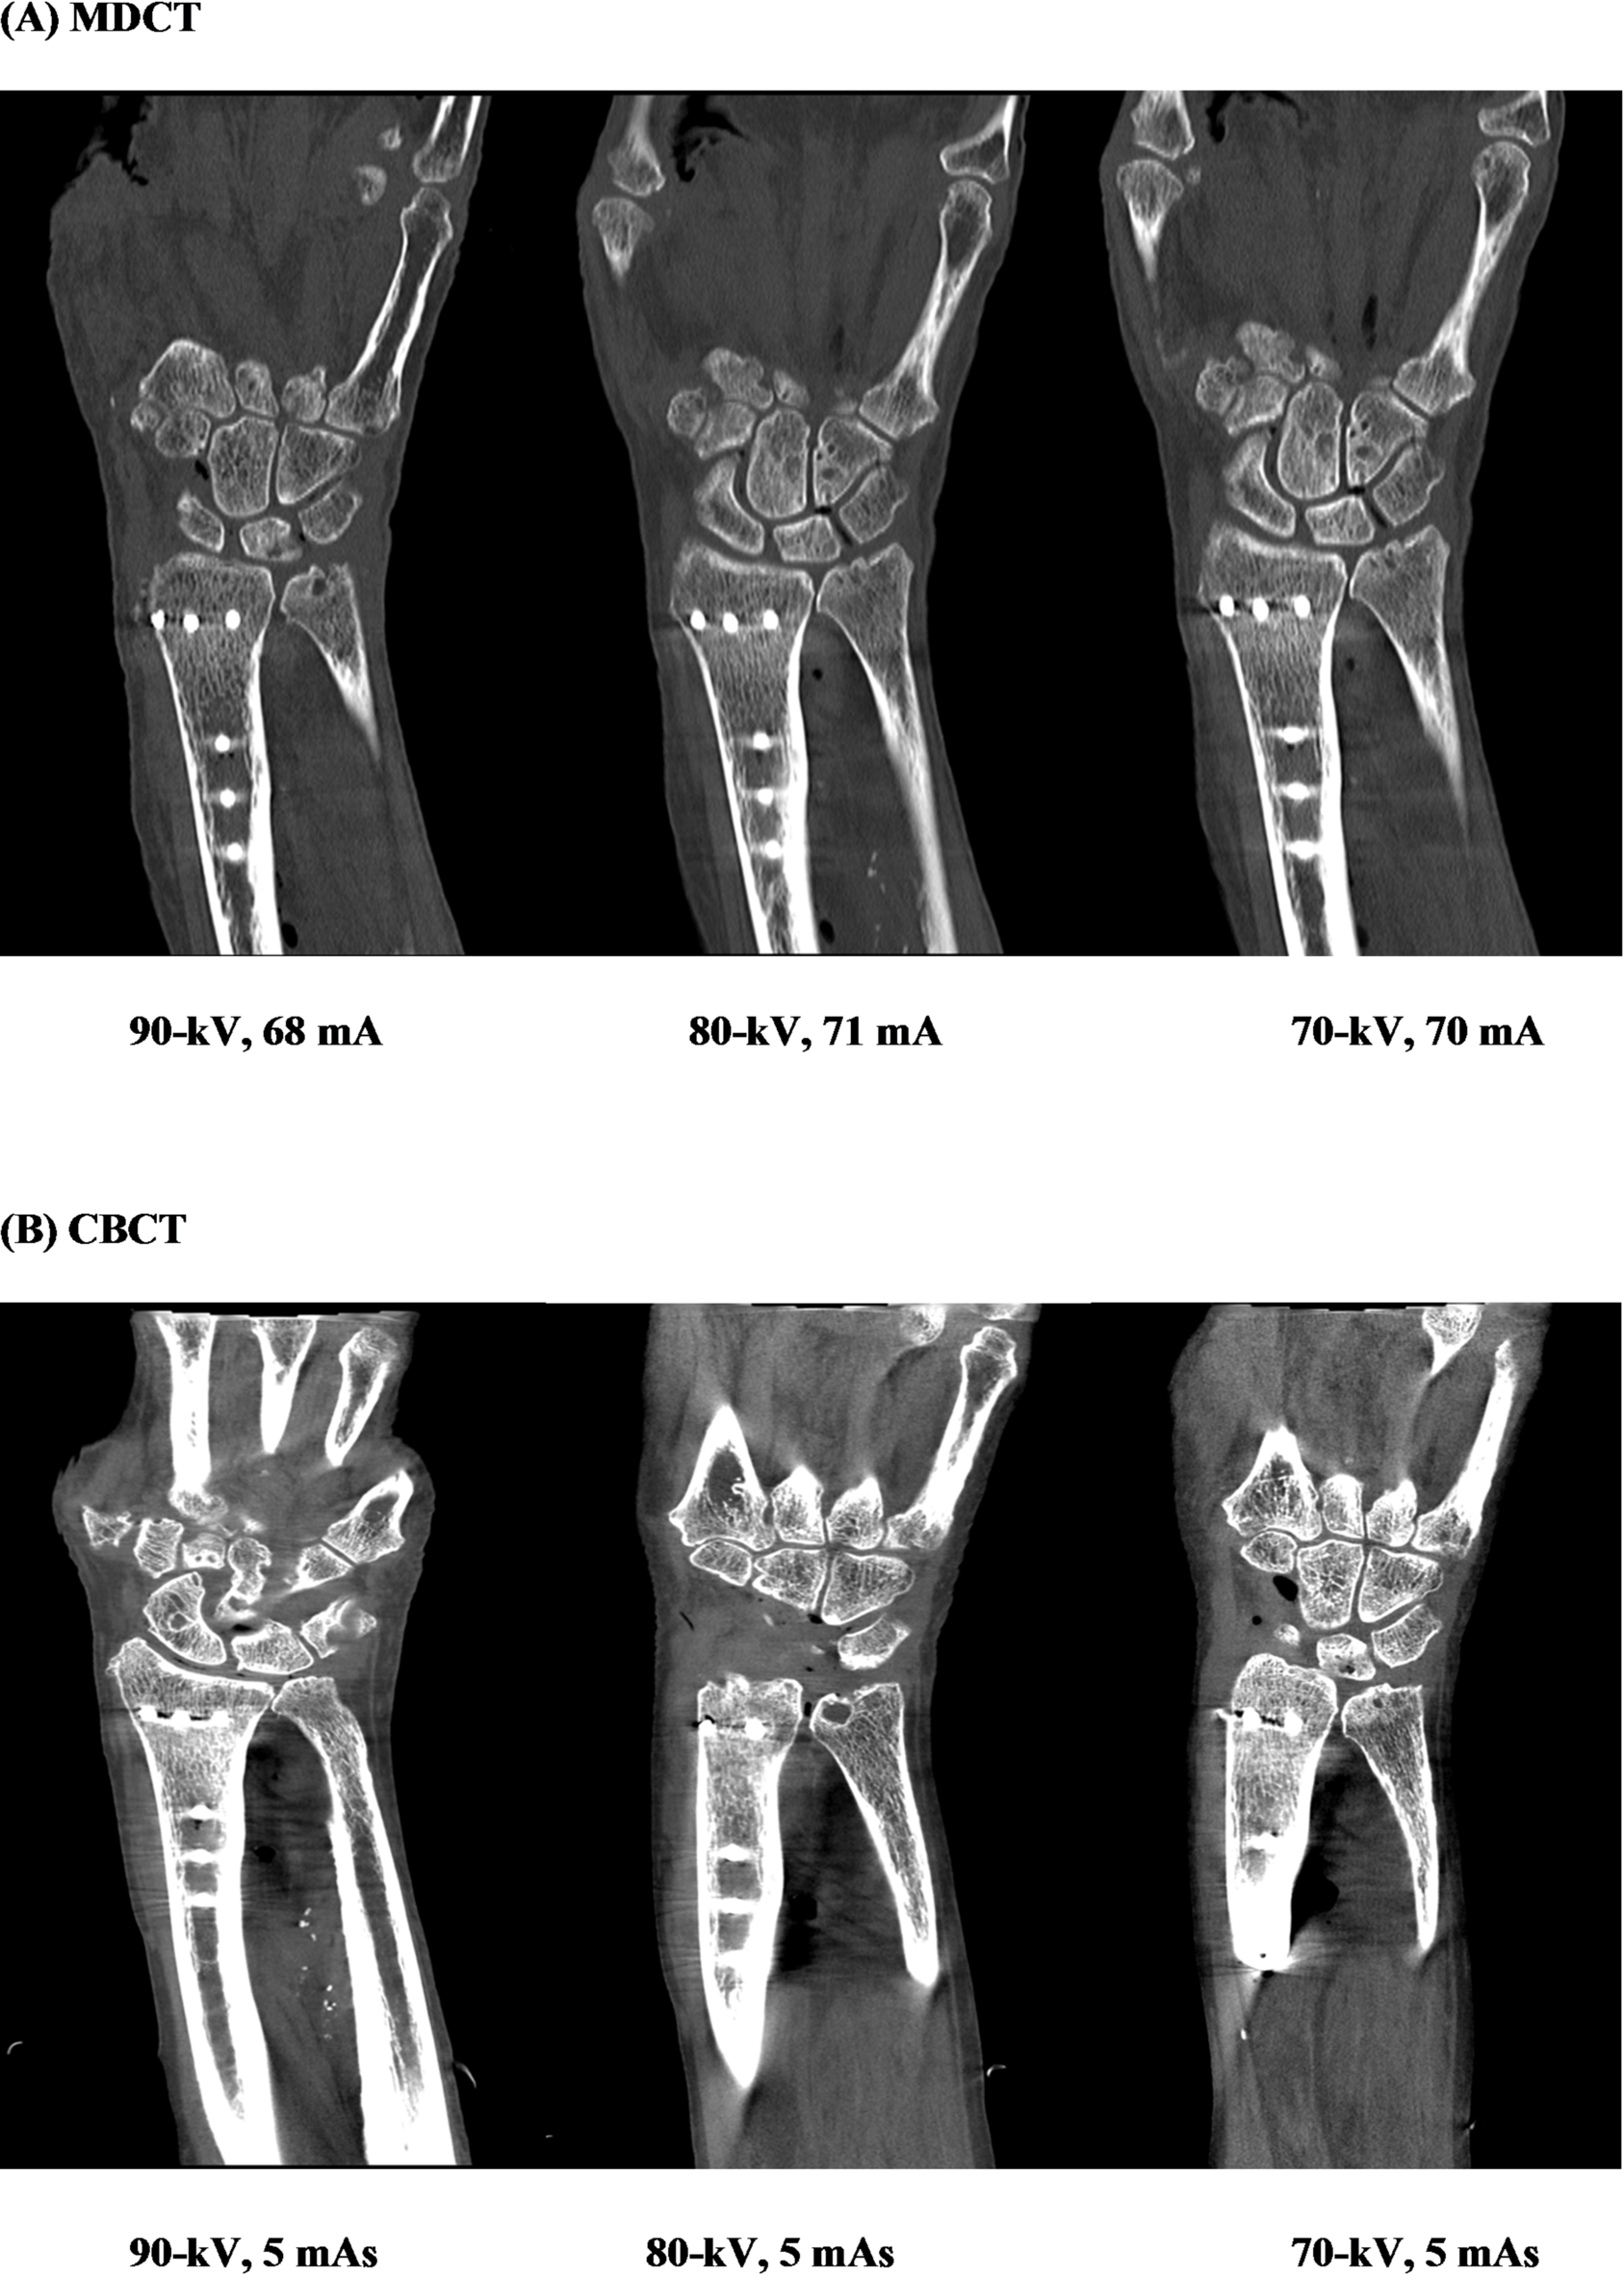

Representative MDCT (A) and CBCT (B) images acquired using different tube voltage and tube current settings. Images illustrate differences in image quality and metal-related artifact expression in the presence of a distal radius plate.